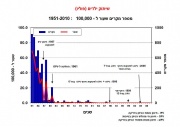

| 08:14, 19 ביוני 2013 | Polio 1951-2010.jpg (קובץ) |  |

73 קילו־בייטים | Motyk | 1 | |